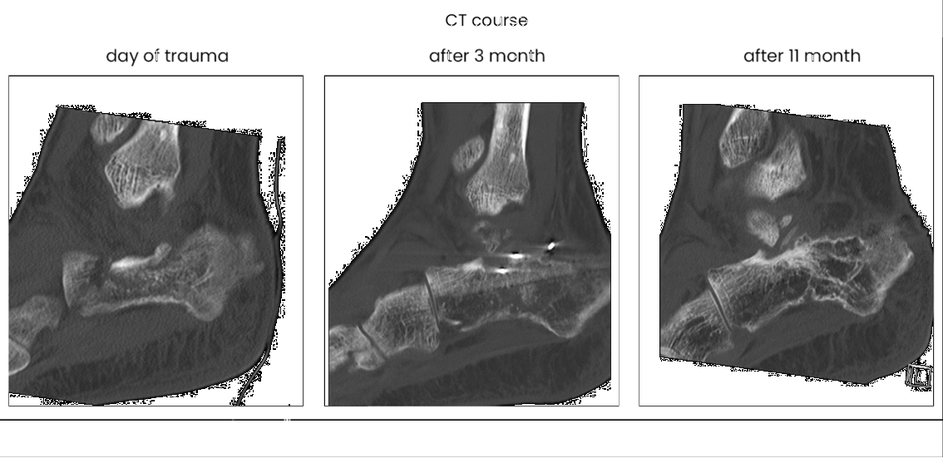

case 17BD, 47 years old, male, fall during work, 2 meters, "comminuted fracture", surgery after 2 days